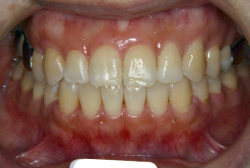

「歯並びの凸凹を直したい」という主訴で来院したケースです。診断の結果、たしかに「叢生」という隙間が足りないと言うことが原因の凸凹症例でした。

しかし、それ以上に問題なのは「前歯の噛み合い方が深すぎる」という症状で、初診の歯の正面写真を見ると下の前歯が全く見えません。こういう症状を矯正学では「過蓋咬合(かがいこうごう)」と言います。過蓋咬合を放置すると、将来的に顎関節に悪影響を与えるとされており、顎関節症の原因因子の一つです。また下の前歯の先端が、上の前歯の裏側の歯茎と強く接触するため、歯周病の原因にもなります。

検査の結果、凸凹が軽症なため非抜歯で矯正すること可能と判断、マルチブラケット装置にて治療しました。治療後は歯並びが綺麗になっただけでなく、噛み合わせ的にも正しい状態が確立しています。